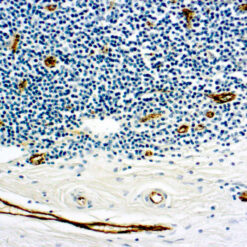

Solitary fibrous tumor (SFT) is a fibroblastic neoplasm of variable biologic potential that can arise at a wide range of anatomic sites. Almost all cases of (98%) including conventional, cellular, atypical, and malignant variants showed nuclear expression of STAT6. Staining for STAT6 was usually diffuse: 68% of cases showed reactivity for STAT6 in 75% of tumor cells. Further, the intensity of staining was strong in 67% of cases, moderate in 25%, and weak in only 7%. The heterogeneity of staining, both in terms of extent and intensity, which may be because of uneven tissue fixation or loss of antigenicity in older cases for which the unstained slides were stored for extended periods of time. All other tumor types examined were negative for STAT6, except for three dedifferentiated liposarcomas and one deep fibrous histiocytoma, which showed weak staining. STAT6 is therefore a highly sensitive and almost perfectly specific immunohistochemical marker for SFT, and can be helpful to distinguish this tumor type from histologic mimics.

| Positive Control Tissue | Solitary fibrous tumor |